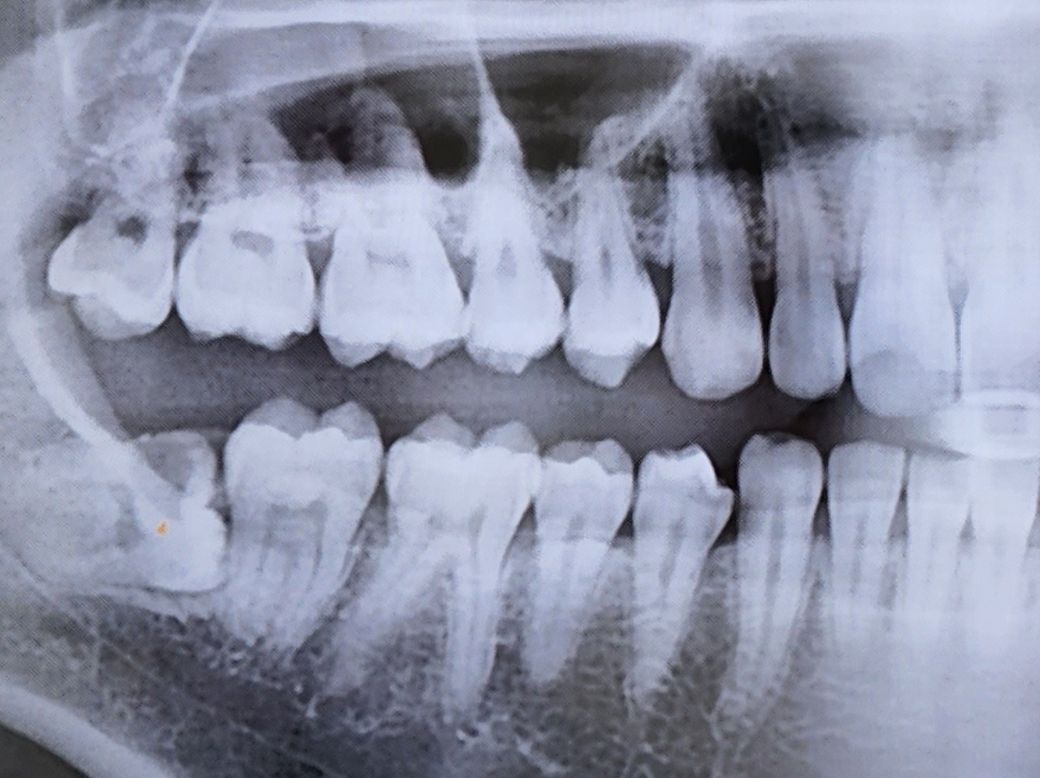

엑스레이 사진 상으로 충치 많아보이나요

상악 하악 6~7번 치아들 눈으로 보면 까만 점이나 까만 실선이나 이런게 보이긴 하는데 엑스레이 사진상으로 법랑질은 괜찮아보이기도 하고.. 또 어떤 의사분은 까맣게 보인다고 충치는 아니라고 하고.. 오우~~~ 누구 말이 맞는가요

일단 사랑니랑 24번 유치는 충치가 확실해서 빼려고 하고 있어요.

어금니 즉 제1대구치와 제2대구치의 교합면(씹는면)의 충치는 x ray 만으로 확인하기

어려우나 치아와 치아 사이 충치(인접면)는 현재 x ray 상에서도 확인됩니다.

충치에 대한 판단은 엑스레이와 직접 눈으로 보는 검사를 통해서 결정하게 됩니다.

사진상으로 치아사이 충치가 몇개가 있는것처럼 보이지만, 정확한것은 눈으로 보면서 최종 판단을 해볼 수 있습니다.

방사선 사진 상에서 까맣게 보인다고 해서 반드시 충치는 아닙니다. 말씀하신 파노라마 사진은 3차원 자료를 2차원으로 나타내기 때문에 방사선에 상당한 왜곡이 있을 수 있으며 방사선 x-ray 및 관구가 통과하는 각도에 따라서 충치가 아닌데도 tearing이 일어나서 검게 보일 수 있습니다.